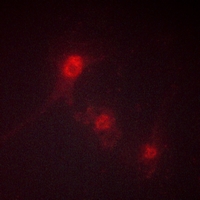

Immunofluorescent analysis of LKB1 (Phospho-S428) staining in NIH-3T3 cells. Formalin-fixed cells were permeabilized with 0.1% Triton X-100 in TBS for 5-10 minutes and blocked with 3% BSA-PBS for 30 minutes at room temperature. Cells were probed with the primary antibody in 3% BSA-PBS and incubated overnight at 4 °C in a hidified chamber. Cells were washed with PBST and incubated with a AF594-conjugated secondary antibody (red) in PBS at room temperature in the dark.